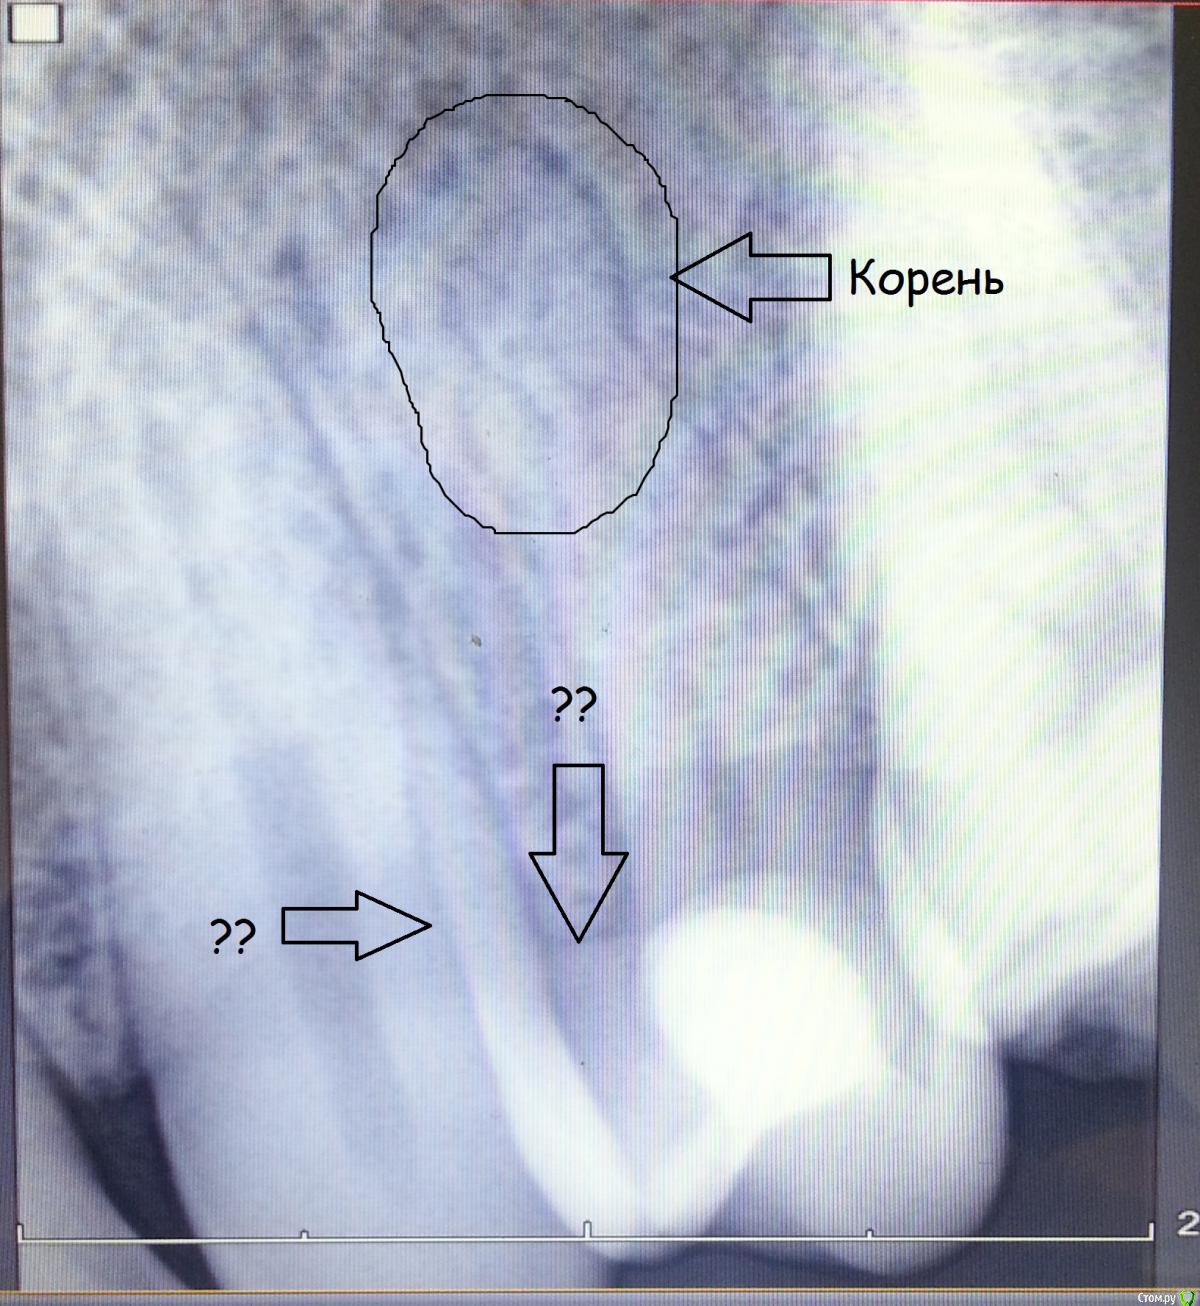

Nitrino1 Опубликовано 16 августа, 2015 Поделиться Опубликовано 16 августа, 2015 (изменено) Здравствуйте коллеги. Обратился пац. Субъективно: боли при давлении на этот зуб. Постоянных болей, спонтанных болей нет.Объективно: отсутствует 24й зуб (аномалия). После 23го сразу 25й. Небольшое покраснение маргинальной десны. Перкуссия 25го болезненна. Холодовой тест отрицательный. Судя по рг там должна быть пломба но внешне как то не определил. Плюс непонятное наложение на клык. Помогите разобраться. Есть мнение что это резорбированная 4ка. Изменено 16 августа, 2015 пользователем Nitrino1 Ссылка на комментарий

Nitrino1 Опубликовано 17 августа, 2015 Автор Поделиться Опубликовано 17 августа, 2015 (изменено) Вот Изменено 17 августа, 2015 пользователем Nitrino1 Ссылка на комментарий